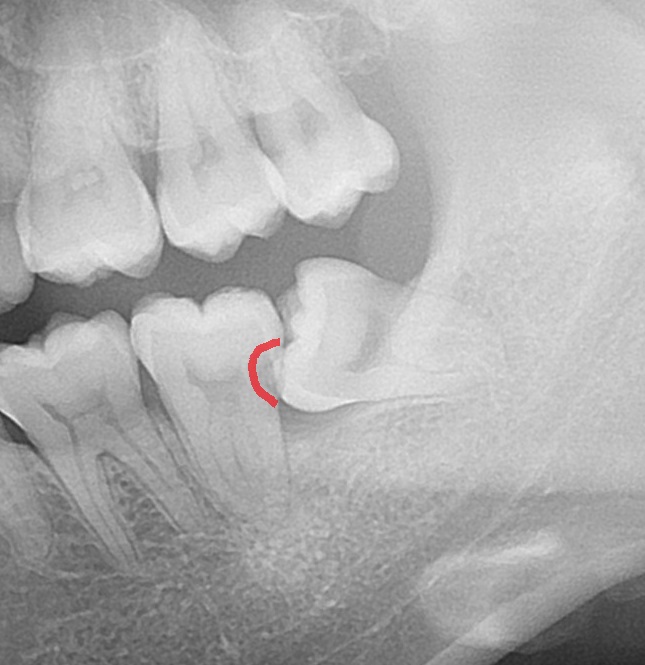

エックス線写真で状況を確認すると

横向きの親知らずが、手前の歯にささっています。

食い込んでいる手前の歯が黒く虫歯になっているのが分かります。

どこかというと、

ここですね。

エックス線で黒く抜ける像が出来ています。

虫歯で歯が溶けています。

歯の側面からの虫歯は神経までの距離が短く、

虫歯が神経まで到達しやすい特徴があります。